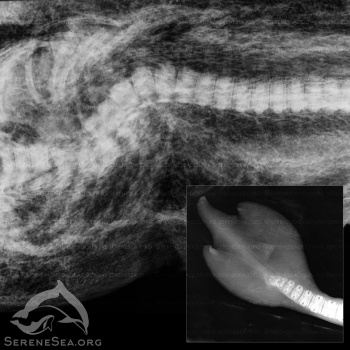

У берегов Алушты местные жители нашли мёртвого новорожденного дельфина-афалину со странным хвостом похожим на трезубец. Как сообщили КИА в центре реабилитации дельфинов «Безмятежное море», аналогичный дельфин был найден у крымского побережья в 2019 году, - передает Керчь.ФМ.

«Эта особенность развития ранее не встречалась в научной литературе по китообразным, но, как мы и предполагали, в Черном море такой дельфин не один. На рентгенографии, помимо особенности строения лопастей, было выявлено сращение хвостовых позвонков. Особенности этих двух дельфинов имеют схожую природу, - не исключено, что они являются родственниками, а врождённая аномалия может быть результатом генной мутации», — отметили в центре «Безмятежное море».

Черноморским дельфинам потенциально угрожает близкородственное скрещивание ввиду низкого генетического разнообразия, что связано с резким сокращением их численности в прошлом. На возможность родства указывает и то, что они были найдены в одном и том же районе.

Обзорный рентген тела найденного в Алуште дельфинёнка выявил перелом позвоночника со смещением, полученный от тупого удара, что привело к смерти особи. В других морях травмы такого характера нередко фиксировались у детенышей, которым не повезло стать мишенью для взрослых агрессивно настроенных самцов.